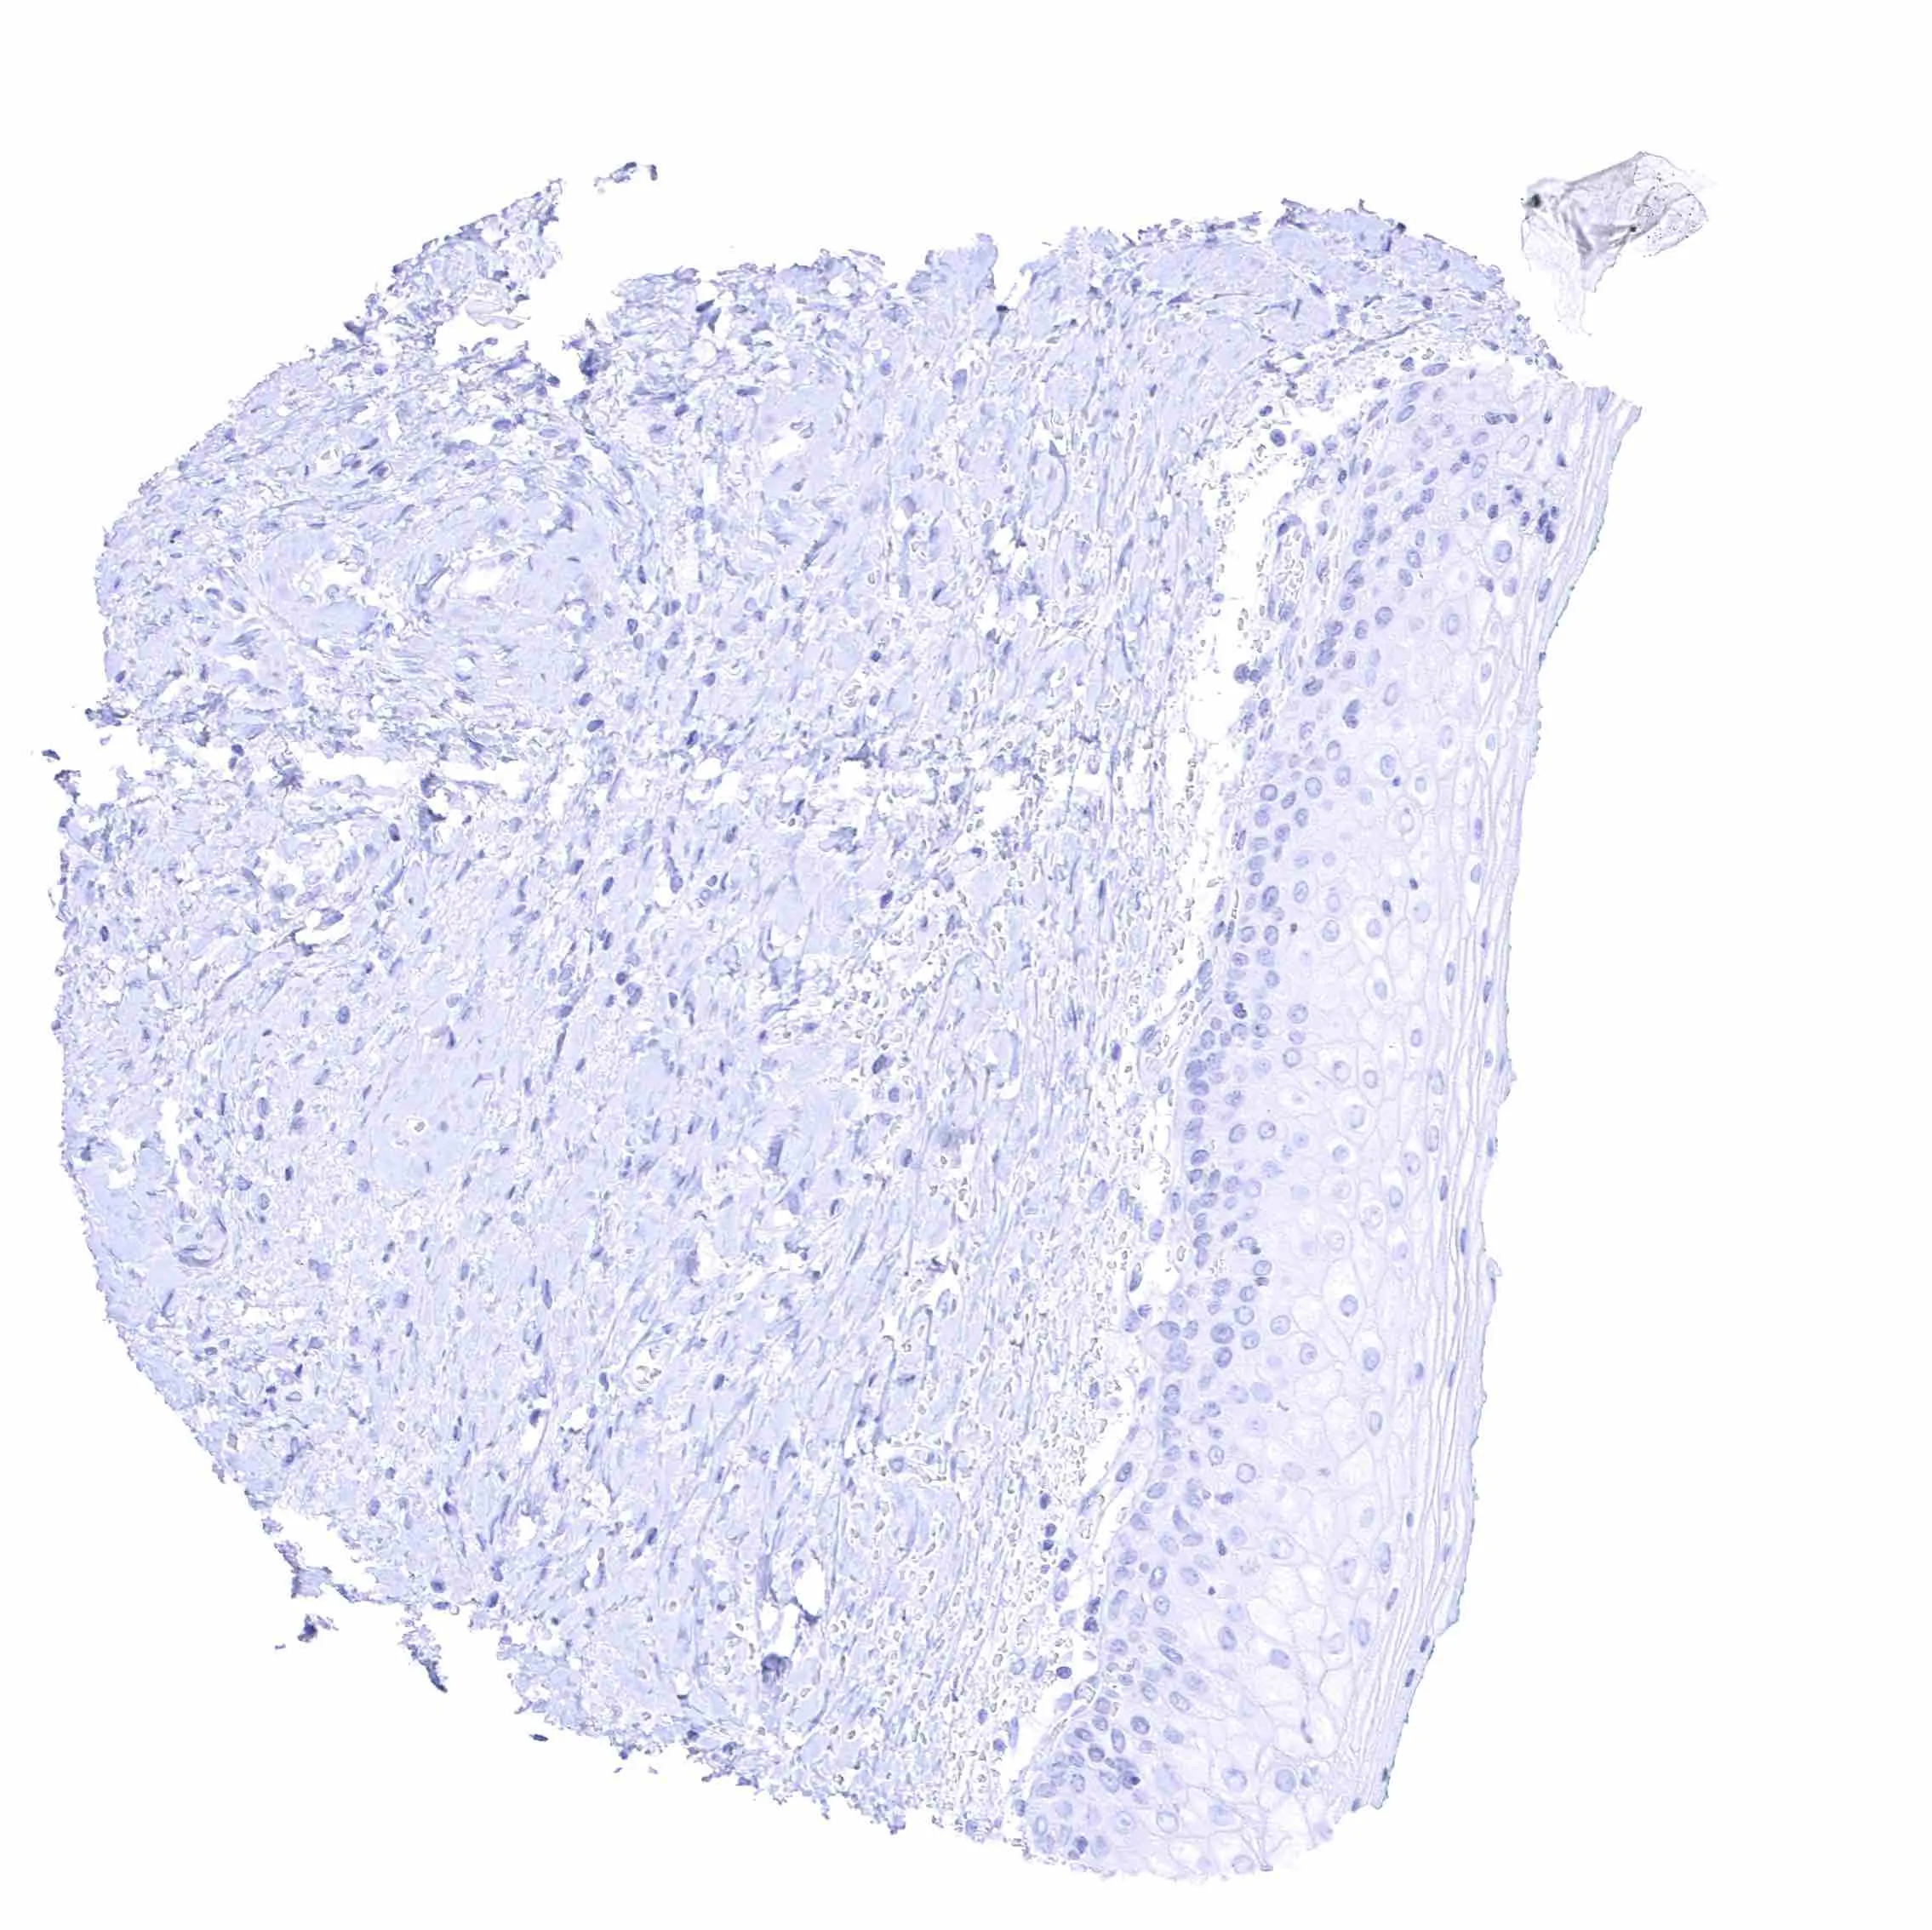

Uterus, ectocervix